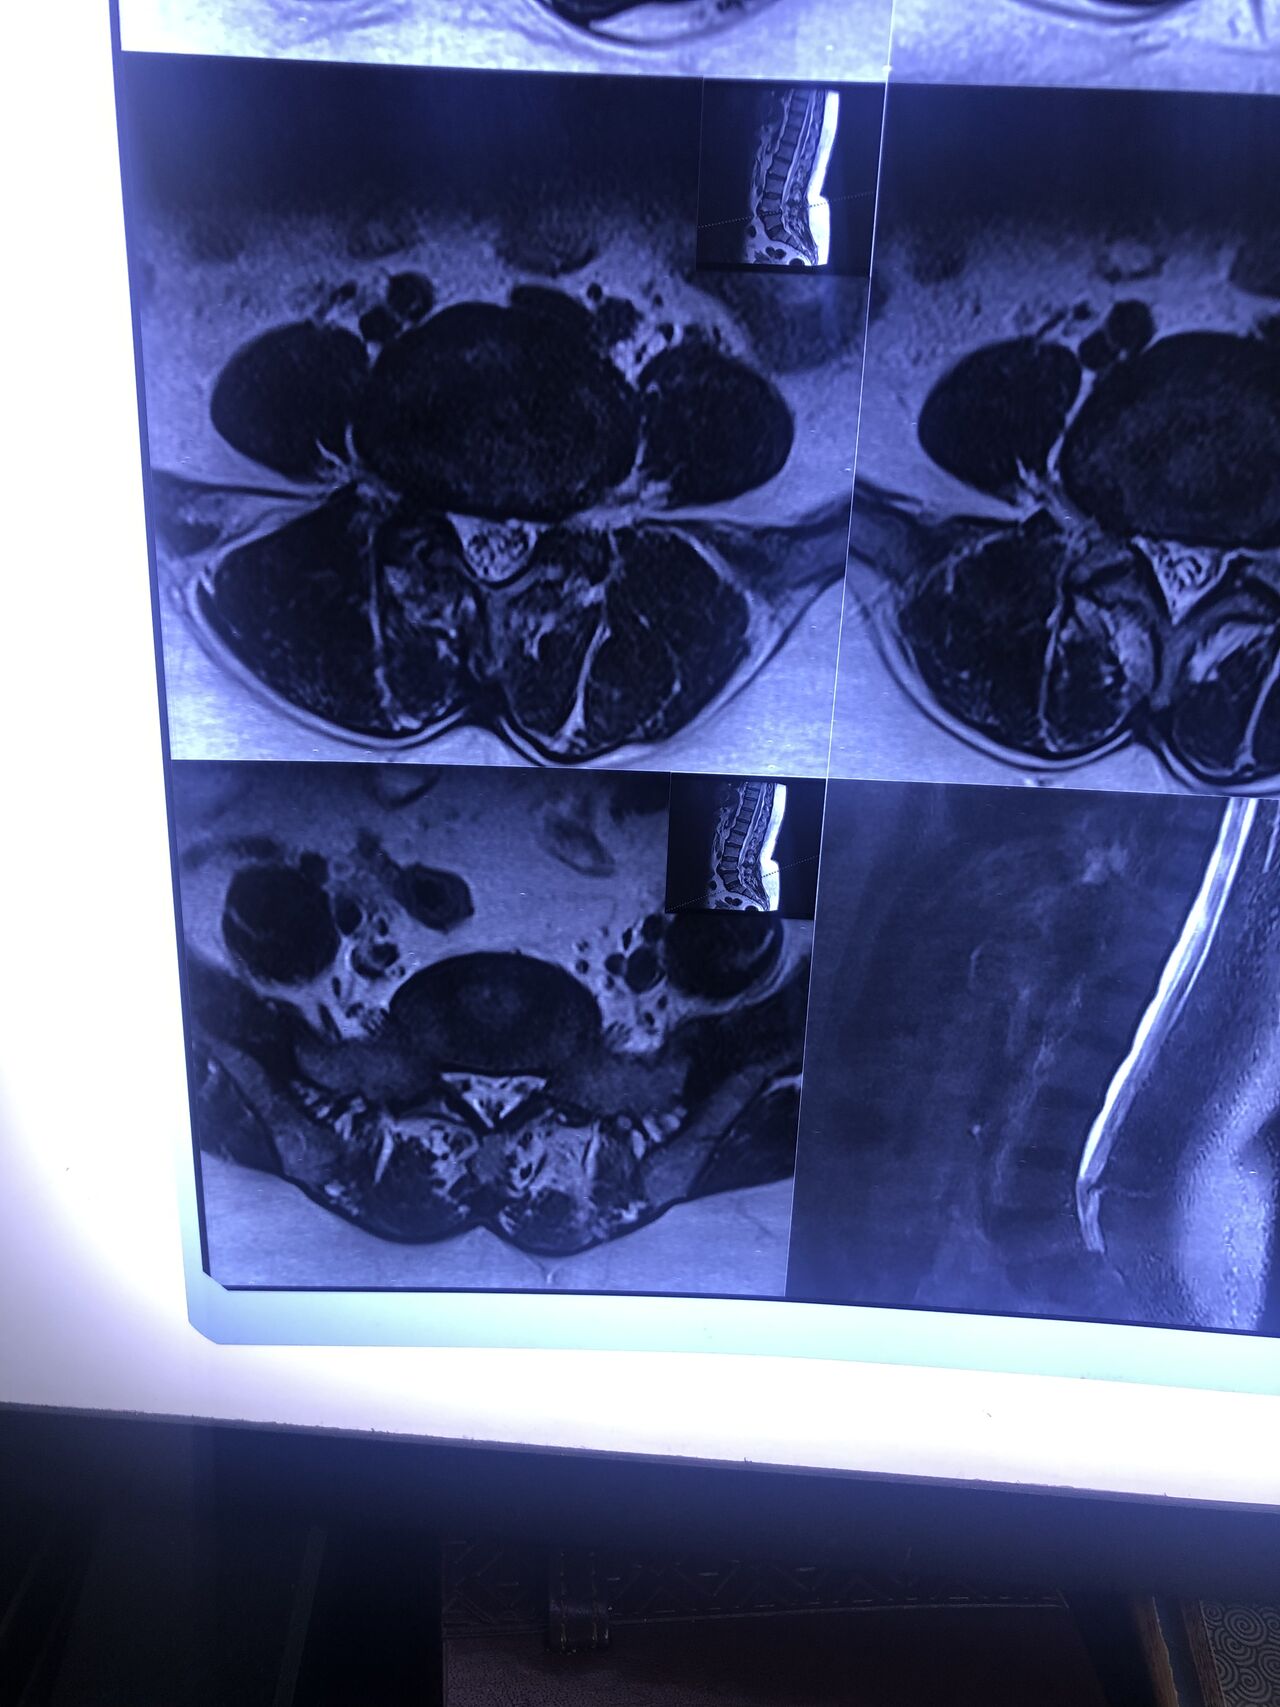

40 yrs old male patient presented to my office who had severe R gluteal pain and radicular pain along R L5-S1 now pain has reduced by 80% in his motor exam had R big toe L5 motor reduced to 4+\5 and R S1 DTR was 0 while L S1DTR was 1+

We did EMG/NCV which showed Mod- sever R L5 S1 irritation without any active axonal loss

I had to decide to refer him for surgery or not patient didn’t have any treatment meanwhile

I ordered new L/S mri

I posted his new mri and old mr

Which was 20 days ago and have posted all below

The first 12 mris had been done 20 days ago

After those first 12 MRIs i have posted new MRIs which were done yesterday

After seeing his new mri and emg/ncv and getting sure his neurological deficit is not active and progressing i told patient he doesn’t need surgery at this time and released him with some advices and exercises

Keep in mind when patient is 80-90 percent pain free and stable i would never give treatment to them just give exercises and follow up their condition